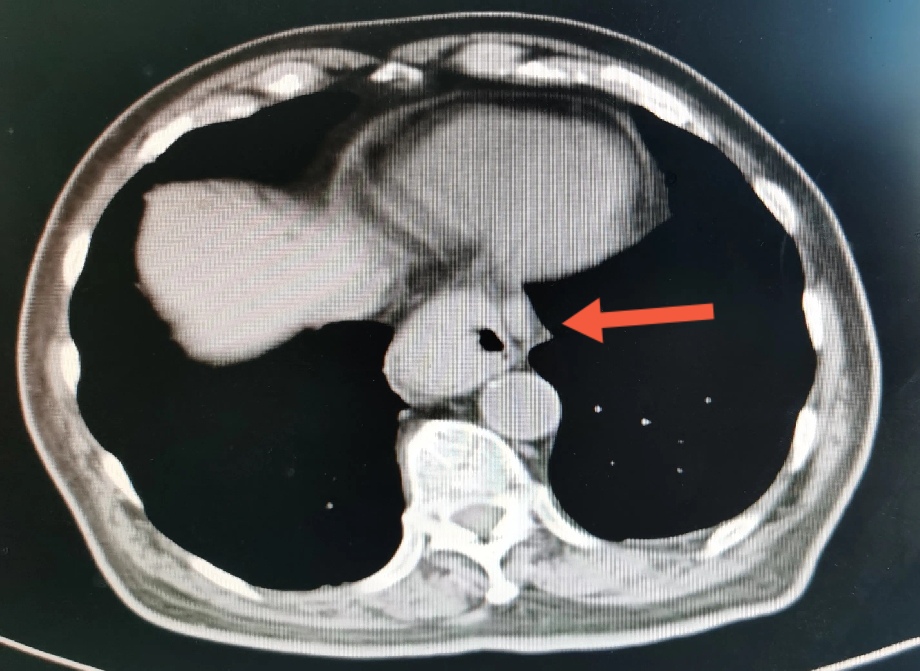

肿瘤旁肿大淋巴结,术后病理证实为肿瘤转移

尽管病情危重,但王老非常坦然,好像把生死看的很淡,笑看人生总是尽力积极配合治疗。王老尽管年龄很大并且做过好几次手术,但是由于平时保养的不错,看上去偏年轻,并且住院后各种检查发现除心脏功能差一点,其它器官功能还可以。化验检查肿瘤标记物甲胎蛋白(AFP)特别高,超过9000ng/ml,考虑是种特殊类型的贲门癌,血色素63g/l,并且胃管里仍时有鲜血引出,腹部CT检查食管下段及贲门区占位,邻近淋巴结肿大,较上次检查明显增大,考虑为转移。因为病情重,连个增强CT都没敢做。